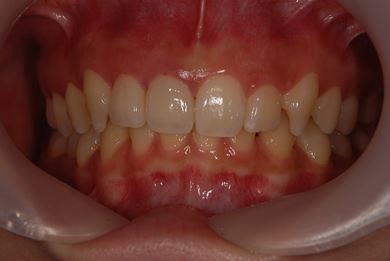

| 性別/年齢 | 女性 / 21歳 | ||||||||||||||||||||||||||||||||

| 主訴 | 歯の変色、欠けた部分を治したい。 | ||||||||||||||||||||||||||||||||

| 治療方針 | 上前歯を根管治療後、オールセラミッククラウンにて審美的回復を行う。 | ||||||||||||||||||||||||||||||||

| 治療内容 | オールセラミッククラウン2本(オールセラミック用土台2本) | ||||||||||||||||||||||||||||||||

| 総治療費 | 286,650円 | ||||||||||||||||||||||||||||||||

| 治療期間 | 4ヶ月 |